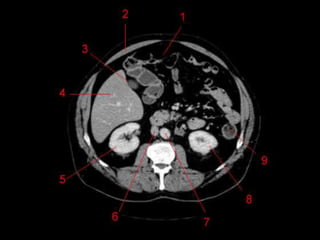

• TC: Tres fases

– Arterial (10 a 20 segundos)

– Fase venosa portal ( 30 segundos )

– Fase venosa hepática (60 segundos)

Técnicas de Imagem •US: Primeiro exame pedido ao: 1) dor no hipocondrio direito; 2) testes de função hepáticas anormais; 3) suspeita de malignidade. • TC: Tres fases – Arterial (10 a 20 segundos) – Fase venosa portal ( 30 segundos ) – Fase venosa hepática (60 segundos) • TC Portografia: Metastases.